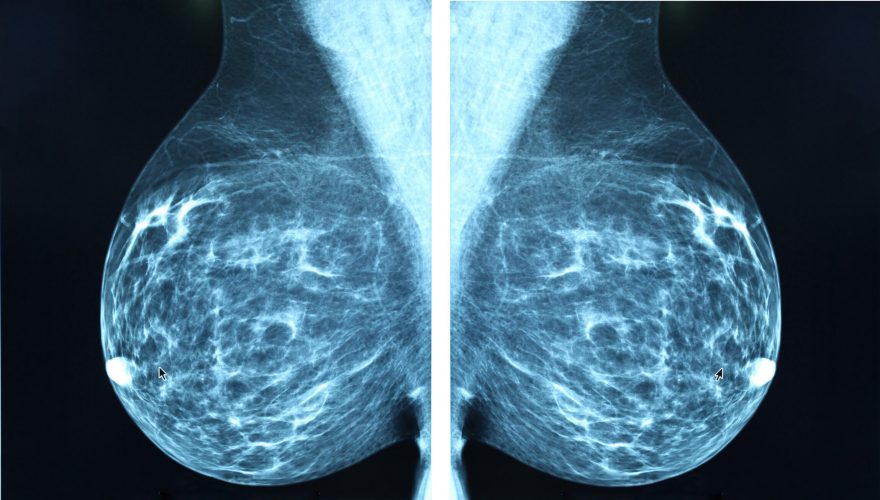

دستگاه اولتراسوند می تواند تصویری ایجاد کند که اغلب به رادیولوژیست اجازه می دهد بین کیست پر از مایع و توده جامد تمایز قائل شود. ماموگرافی این تمایز را ایجاد نمی کند، اگرچه در تشخیص میکروکلسیفیکاسیون ها که می تواند نشانه اولیه سرطان سینه باشد، بهتر از سونوگرافی است.

سونوگرافی پستان به تشخیص توده های پر از مایع در سینه (کیست) از توده های جامد که ممکن است سرطانی یا خوش خیم (غیر سرطانی) باشند، کمک می کند. معاینه سینههای زنان جوانتر اغلب مفید است، زیرا بافت پستان بسیار متراکمتر از زنان مسنتر است و این تراکم میتواند تشخیص یک ناهنجاری را در صورت انجام ماموگرافی سختتر کند.

ماموگرافی یک اشعه ایکس است که به شما امکان می دهد ساختار داخلی سینه ها را برای تشخیص هر گونه ناهنجاری تجسم کنید. در این روش از اشعه ایکس استفاده می شود. این می تواند توسط یک پزشک عمومی یا متخصص در صورت بروز ناهنجاری در لمس پستان، برای معاینه یا به عنوان بخشی از کمپین های غربالگری سازمان یافته تجویز شود. ماموگرافی را می توان در صورت لزوم با سونوگرافی پستان تکمیل کرد: این یک ارزیابی طبیعی سنولوژیک است.

سونوگرافی پستان برای تعیین اینکه آیا توده ای که در طول ماموگرافی یافت می شود از بافت جامد ساخته شده است یا پر از مایع است استفاده می شود. سونوگرافی از پستان یک تصویر داخلی و در زمان واقعی از ساختار سینه ایجاد می کند و می تواند جریان خون را نشان دهد. اولتراسوند روشی غیر تهاجمی برای یافتن اطلاعات بیشتر در مورد توده یا توده ای است که در پستان یافت می شود و به تعیین مراحل بعدی مراقبت کمک می کند.

ماموگرافی از اشعه ایکس برای تصویربرداری از پستان استفاده می کند. هم سرطان و هم بافت متراکم در اشعه ایکس سفید به نظر میرسند، که تشخیص سرطان را در زنان با سینههای متراکم با استفاده از ماموگرافی دشوار میکند.